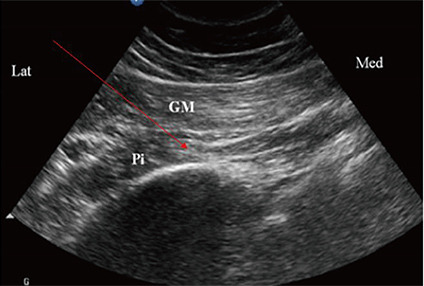

- 최근에는 이상근 증후군이 의심되면 진단과 치료를 동시에 할 수 있는 근육 신경 자극술을 시행합니다. 근육 신경 자극술이란 통증의 원인이 되는 근육, 신경, 관절 부위를 IMS 용 바늘로 자극하여 치료하는 통증 시술로 뭉친 이상근 근육을 바늘로 풀어주는 치료입니다. 특히 이 치료는 약물이 안 들어가기에 부작용이 없는 것이 최대 장점입니다. 그리고 효과 면에서 약이나 도수 치료, 물리치료보다 훨씬 더 탁월합니다. 특히 환자를 치료할 때 아래 그림에서 보듯이 초음파 유도하에 치료를 많이 하고 있습니다. 그러면 이상근 정확한 부위에 혈관 신경을 피하여 오차 없이 안전하게 시술할 수 있습니다.